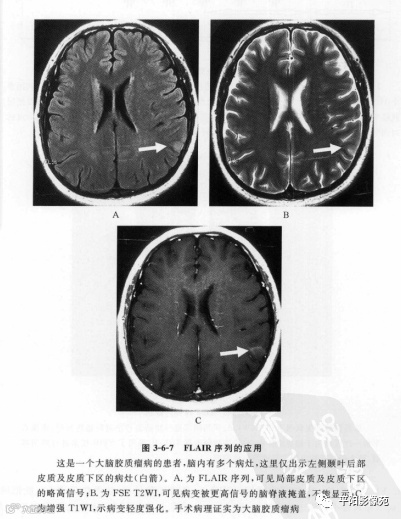

2. FLAIR序列

在脑部或脊髓T2WI上,当病灶相对较小且靠近脑脊液时,呈现略高信号或高信号的病灶常常被更高信号的脑脊液掩盖,如果在T2WI上能把脑脊液的信号抑制下来,病灶就能充分暴露。液体抑制反转恢复(fliud attenuated inversion recovery,FLAIR)即黑水序列可以有效地抑制脑脊液信号(图3)。在临床实际应用中,1.5T扫描机一般TI选为2100~2500ms,TR需要大于TI的3~4倍,ETL及有效TE与FSE T2WI相仿。